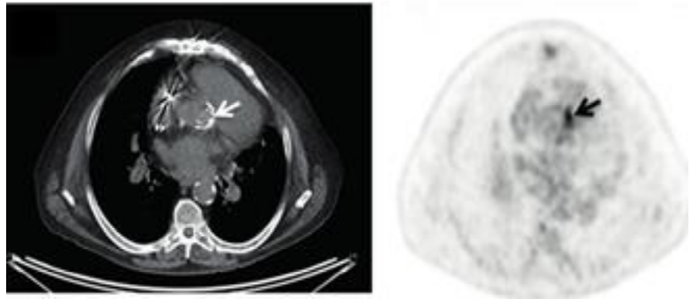

Atenção: o caso a seguir refere-se a próxima questão.

Homem de 70 anos, portador de prótese aórtica biológica há 4 anos, comparece à consulta com queixa de emagrecimento de

6kg em 2 meses, associado à sudorese noturna, febre não aferida e cansaço progressivo. Em uso apenas de ácido acetilsalicílico e

atorvastatina.

Ao exame: emagrecido, eupneico, hipocorado 2+/4+, desidratado. Dentes em mau estado de conservação. TAX: 39ºC, FC: 105 bpm, PA:

130x60 mmHg; ausência de linfonodomegalias ou alterações cutâneas; ausculta pulmonar sem ruídos adventícios; ritmo cardíaco regular

em 2 tempos, bulhas normofonéticas, sopro sistólico 3+/6+ em foco aórtico, com irradiação carotídea; espaço de Traube submaciço.

Membros inferiores sem edema.

Iniciada antibioticoterapia empírica após coleta de 3 pares hemoculturas de sítios diferentes, para aeróbios e anaeróbios. Ecocardiograma

transtorácico sem vegetações nas válvulas nativas, porém sem visualização adequada da válvula aórtica.

Após 3 dias, houve crescimento de Streptococcus mitis em 4 frascos de hemoculturas, de três sítios de coleta diferentes. Complementada a

investigação com uma tomografia computadorizada por emissão de pósitrons, que se encontra a seguir.